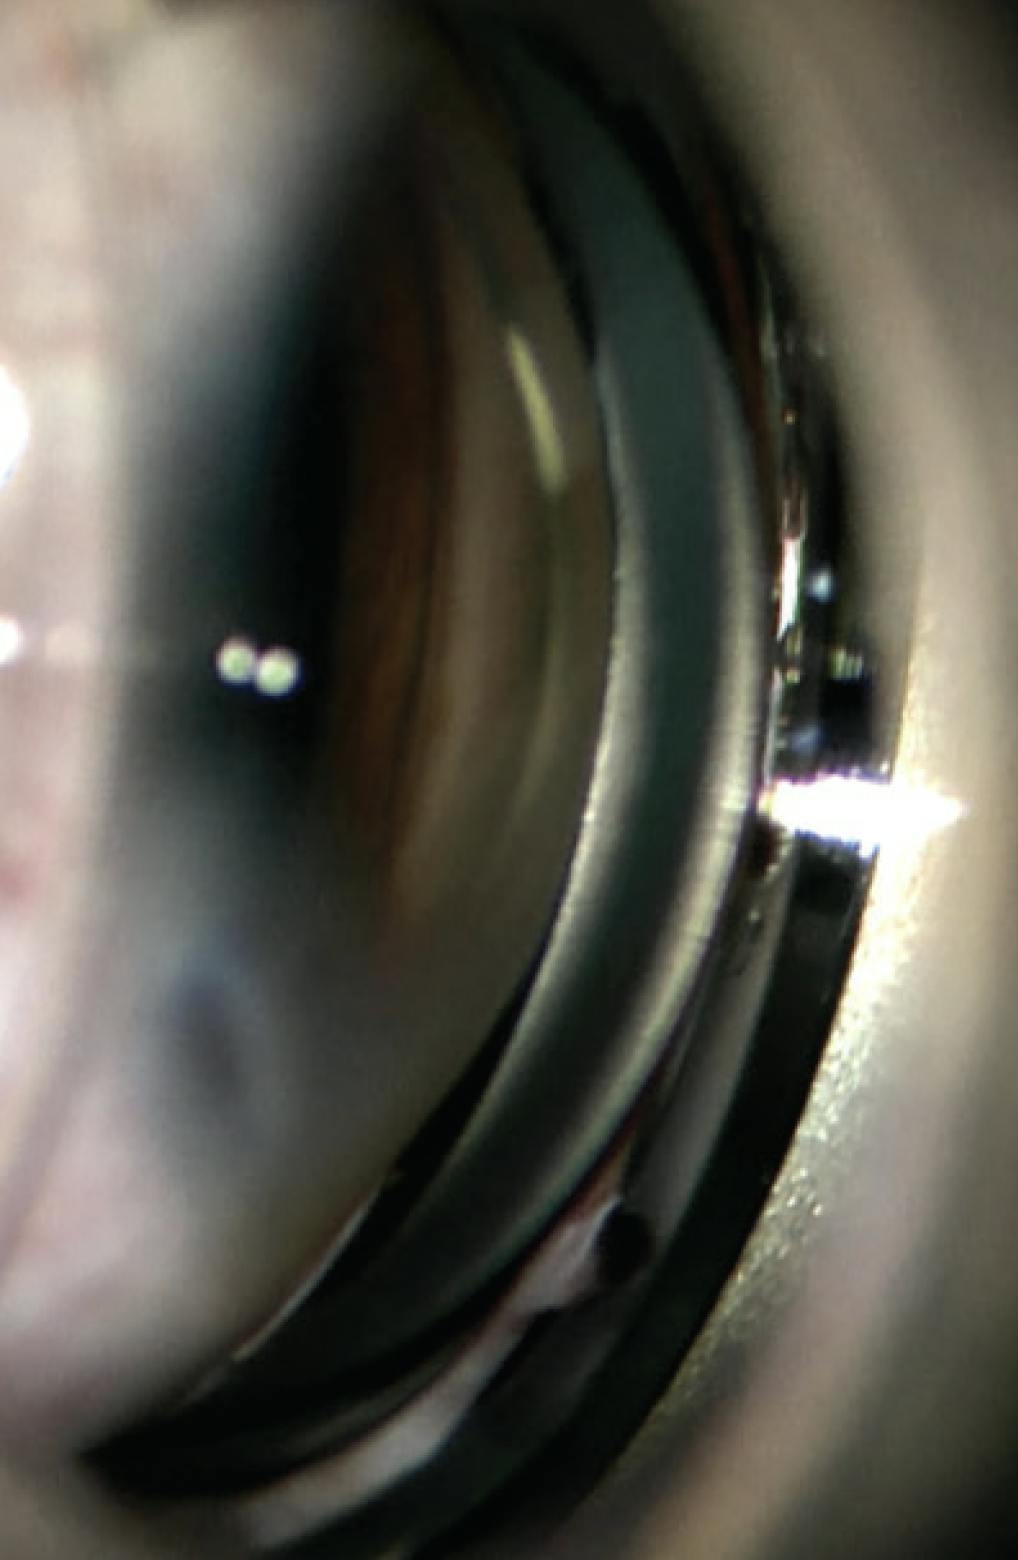

One week after surgery, his IOP was 15 mm Hg OU, and his UCVA was 20/150 OD and 20/40 OS. Topical glaucoma medications were stopped. Gonioscopy of the right eye revealed an open angle for 270º (Figure 2) and some residual PAS.

<p>Figure 2. Postoperative gonioscopy reveals an open angle and well-pigmented trabecular meshwork from prior apposition to the iris.</p>

Figure 2. Postoperative gonioscopy reveals an open angle and well-pigmented trabecular meshwork from prior apposition to the iris.